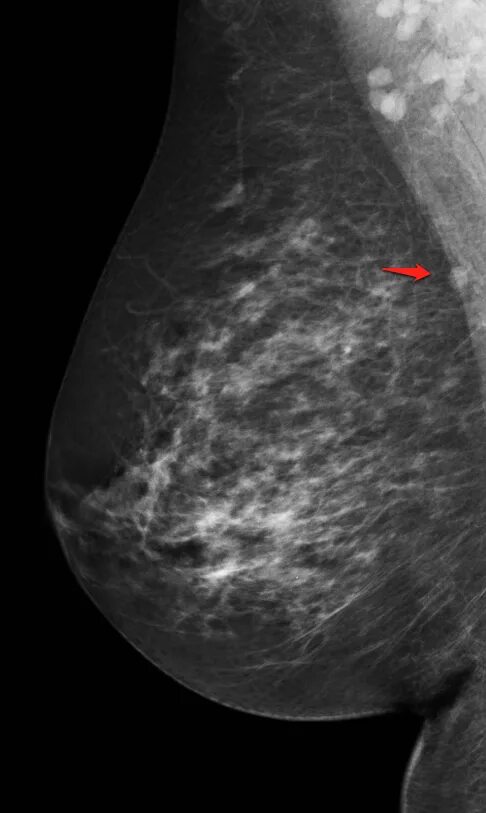

Какой лимфоузел при раке молочной железы